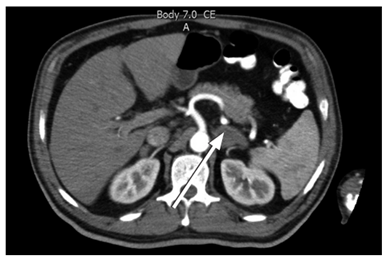

Se inició el manejo médico inmediato con hidratación intravenosa (IV) y en su estudio paraclínico llamó la atención la presencia de un reporte de cortisol sérico de las 8 a.m. en 0,0 µg/dL, hiponatremia con valor de sodio sérico en 125 mmol/L e hiperpotasemia severa con potasio sérico en 7 mmol/L (sin alteraciones electrocardiográficas). Otros exámenes reportaron hiperfosfatemia con valor de 5,9 mg/dL, hiperuricemia con ácido úrico en 8,57 mg/dL y elevación de los valores de creatinina sérica en 1,36 mg/dL. Con todos los datos anteriores, se consideró un paciente en crisis adrenal con deterioro de función renal e hiperfosfatemia con hiperuricemia. Se inició el manejo inmediato con hidrocortisona y se mantuvo el soporte constante de líquidos y electrólitos, frente a lo cual mejoró la hipotensión, hiponatremia e hiperpotasemia. Se realizaron estudios imagenológicos con una TAC de abdomen contrastada en la que se evidenció engrosamiento marcado de ambas glándulas suprarrenales, principalmente la izquierda, con realce homogéneo del medio de contraste, pero con una lesión aparentemente focal de la glándula suprarrenal izquierda que medía 21 mm. También se evidenciaron ganglios de las cadenas inguinales bilaterales ligeramente aumentados de tamaño (Figura 1).